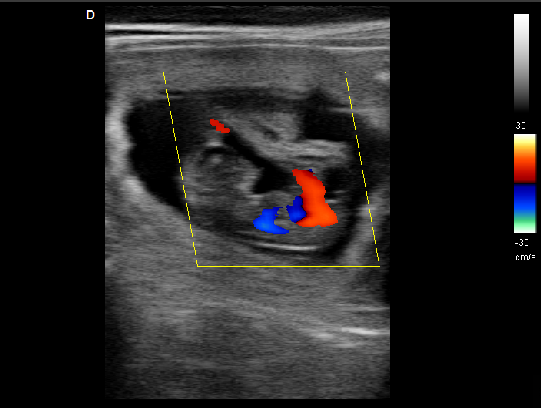

P5-VET便攜獸用彩超機頸動脈檢查圖

頸動脈血流:

頸動脈彩超是診斷、評估頸動脈壁病變的有效手段之一,在動脈粥樣硬化的流行病學調查和對動脈粥樣硬化預防、治療試驗的有效性評價中起著關鍵作用。

頸動脈彩超不僅能清晰顯示血管內中膜是否增厚、有無斑塊形成、斑塊形成的部位、大小、是否有血管狹窄及狹窄程度、有無閉塞等詳細情況, 并能進行準確的測量及定位,還能對檢測動脈的血流動力學結果進行分析。